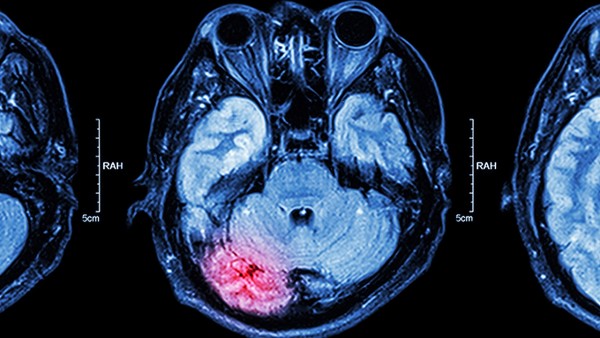

脑外伤因损伤的轻度和损伤部位不同而出现后遗症。常见的后遗症有瘫痪、癫痫、消化道出血等。为了预防脑外伤后遗症的发生,需要做好受伤后的恢复工作,经常锻炼身体,预防下肢僵硬和肌肉萎缩。

脑外伤后遗症

1、出现肢体的瘫痪,严重的可以导致出现昏迷成为植物人,还有一些会引起脑内异常的放电,从而导致出现反复的肢体抽搐形成癫痫。